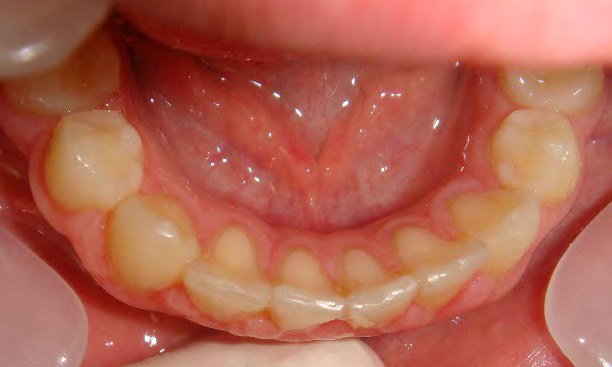

Below are cases treated at Vakresmil without extractions within the last three years. The families had been told, “It is simply not possible for your child to be treated without extractions” by orthodontists. Judge for yourself if that was right or wrong.

The overall aim is to produce the best smile we can — a “beautiful smile”, if you will — without premolar extractions, headgear, facemasks or banded appliances. A smile that both the patient and we at Vakresmil can be proud of.